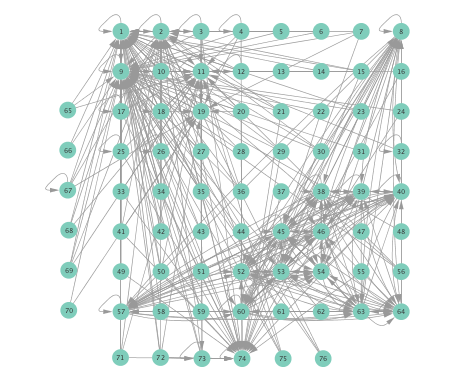

VI-B Inferred networks

Prior to running the developed algorithm, s intervals were chosen from the preprocessed ECoG data, and then divided into successive segments, each spanning s. To illustrate this, suppose the s interval starts from s and ends at , then the first segment comprises samples taken over the interval , the second one would be , and so on. After this segmentation of the time series, directed network topologies were inferred using Algorithm 1 with , based on the s segments, instead of the entire signal, to ensure that the signal is approximately stationary per experiment run. A directed link from electrode to was drawn if at least one of the estimates of turned out to be nonzero.

Networks inferred from the preictal and ictal intervals were compared using the linear, the kernel-based (K-)SVARMs, as well as the K-SVARM with data-driven kernel selection. The lag lengths were set to for all cases. For the K-SVARM, a polynomial kernel of order was selected. Furthermore, the threshold in Algorithm 1 was set to , was set to , while the regularization parameter was selected via cross-validation. For the data-driven kernel selection scheme, two candidate kernels were employed, namely, a linear kernel, and a polynomial kernel of order .

Figure 2 depicts networks inferred from different algorithms for both preictal and ictal intervals of the time series. The figure illustrates results obtained by the linear SVARM, and the K-SVARM approach with and without kernel selection. Each node in the network is representative of an electrode, and it is depicted as a circle, while the node arrangement is forced to remain consistent across the four visual representations. A cursory inspection of the visual maps reveals significant variations in connectivity patterns between ictal and preictal intervals for both models. Specifically, networks inferred via the K-SVARMs, reveal a global decrease in the number of links emanating from each node, while those inferred via the linear model depict increases and decreases in links connected to different nodes. Interestingly, the K-SVARM with kernel selection recovered most of the edges inferred by the linear and the K-SVARM using a polynomial kernel, which implies that both linear and nonlinear interactions may exist in brain networks. Clearly, one is unlikely to gain much insight only by visual inspection of the network topologies. To further analyze differences between inferred networks from both models, and to assess the potential benefits gained by adopting the novel scheme, several network topology metrics are computed and compared in the next subsection.